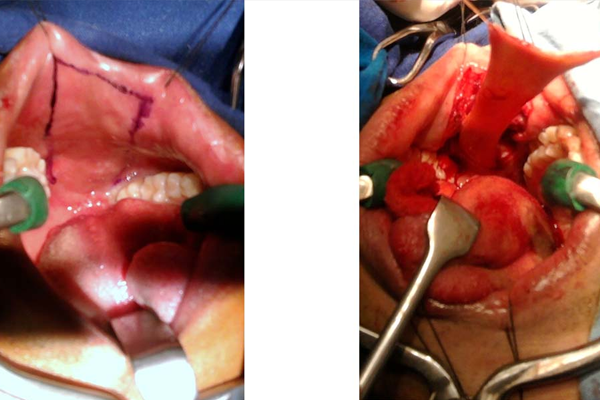

HARVESTING BUCCAL MUCOSA FOR FULL LENGTH BARBAGLI’S URETHROPLASTY